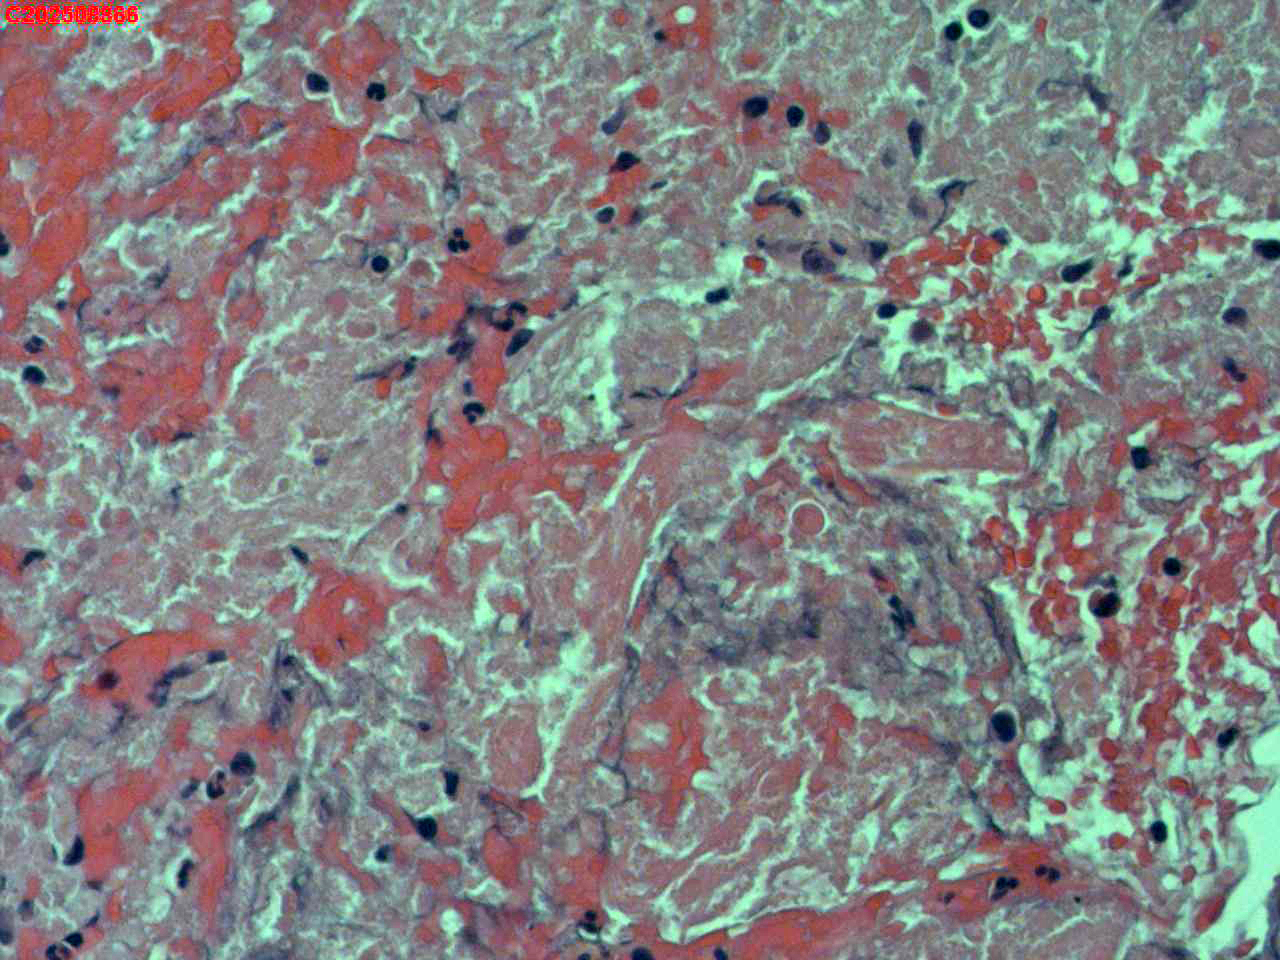

纤支镜咬检

肺TB?Ca?

胸部CT(平扫):考虑双肺感染性病变,结核?支气管炎?请结合临床及其它检查。

标本名称

右肺上叶后段开口咬检组织

大体所见

右肺上叶后段开口处粘膜不规则增生。

肉芽肿性炎的可能性大些!

有坏死,深染变形的细胞需要排一排神经内分泌肿瘤。